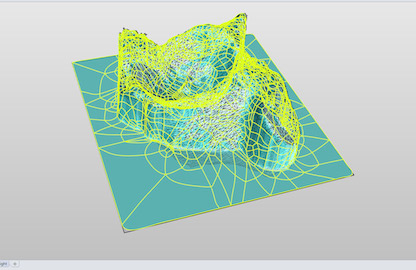

Optimized Ortho engaged Park Industrial to enable the second stage of their implant positioning system. We created surgical guides uniquely shaped to match the pelvis of each patient that were derived from X-ray and CT scan data. These guides are then fabricated from the latest 3D printing techniques using biocompatible materials.

Park Industrial developed an automated system of guide design that was created using Python scripts and the Solidworks API. This helped to realise the commercial viability of the technology.